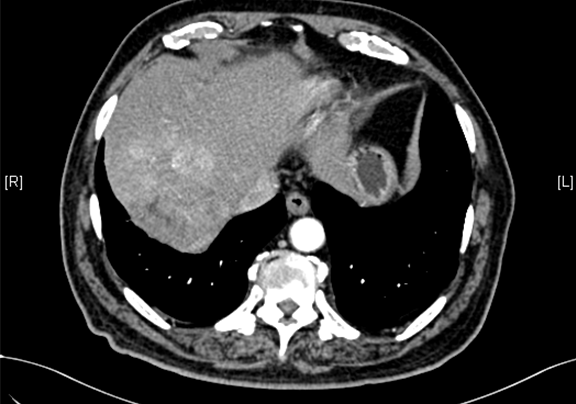

术前CT检查:

动脉期

下腹部增强CT示:肝右后叶上段占位,肝癌可能性大;右侧肾上腺占位,不除外转移瘤。